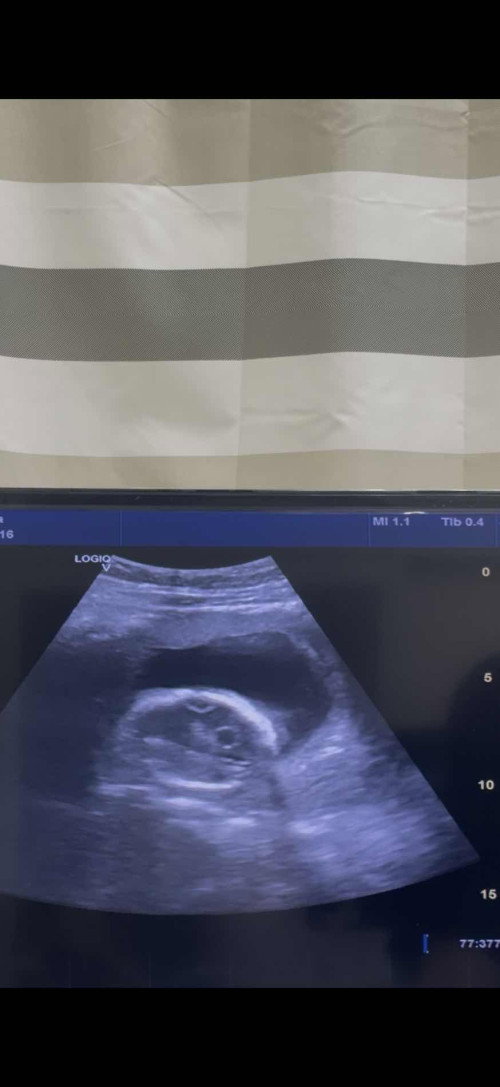

ตอนนี้6w5d ช่วยดูได้มั้ยคะว่าสีขาวๆในถุงตั้งครรภ์ใช่ตัวอ่อนหรือถุงไข่แดงมั้ย 1อาทิตย์ที่แล้วซาวด์ดูถุงตั้งครรภ์0.93 อาทิตย์นี้1.58 ใหญ่ขึ้น มีโอกาสท้องลมมั้ยคะ หมอนัดอีกทีเดือนหน้าเลยค่ะ เครียดค่ะ😣